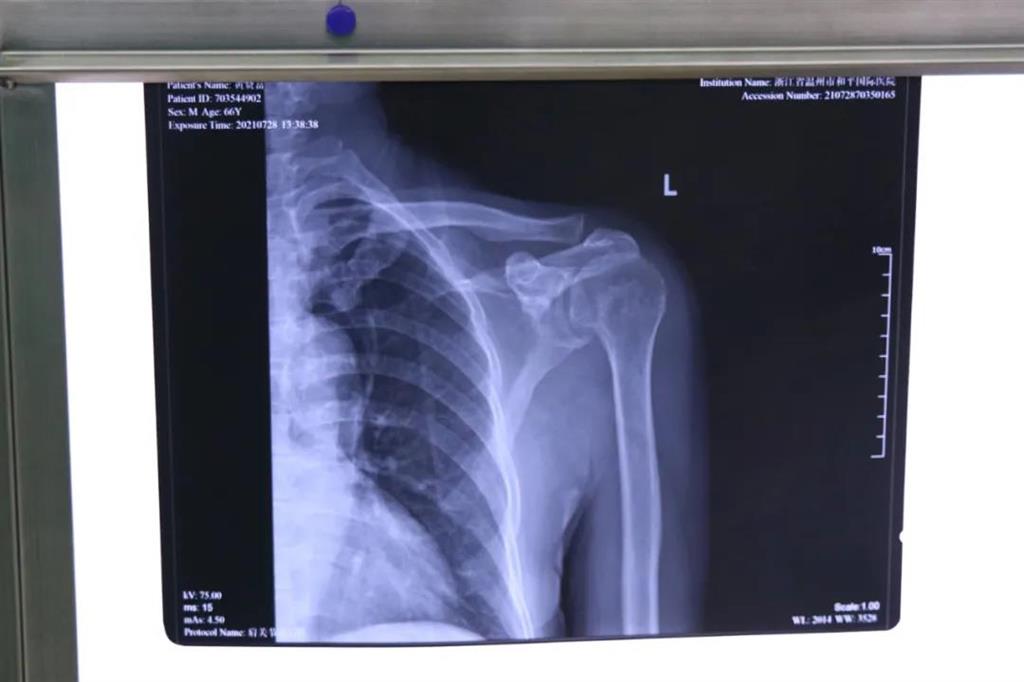

患者黃大叔(66歲)為"左肩袖損傷"病人,8年來左肩部持續(xù)疼痛伴肩關(guān)節(jié)活動輕微受限。患者于近期左肩部疼痛加重,抬肩困難,難以完成穿衣服等日常生活活動。

術(shù)前檢查見左肩關(guān)節(jié)輕度腫脹,左肩關(guān)節(jié)岡上肌附著處壓痛明顯,MRI提示左岡上肌肌腱斷裂回縮,岡下肌腱部分撕裂。為此和平國際醫(yī)院關(guān)節(jié)鏡微創(chuàng)團(tuán)隊(duì)為患者制定了詳細(xì)的一期、二期手術(shù)方案。此次手術(shù)為一期肩袖成形術(shù)

常規(guī)手術(shù)方式是傳統(tǒng)切開肩袖縫合術(shù),但缺點(diǎn)就是創(chuàng)傷較大,切口較大,術(shù)后康復(fù)困難,視野較小,難以處理其他合并傷。目前更先進(jìn)的技術(shù)是采取肩關(guān)節(jié)鏡微創(chuàng)手術(shù),術(shù)中探查肩袖撕裂口,并將其縫合固定

在和平國際醫(yī)院關(guān)節(jié)鏡微創(chuàng)團(tuán)隊(duì)的協(xié)作下,手術(shù)順利,成功用微創(chuàng)肩關(guān)節(jié)鏡進(jìn)行肩袖修補(bǔ)術(shù)。術(shù)中、術(shù)后患者幾無出血,且手術(shù)切口小,美觀,患者左肩部疼痛得到明顯緩解。